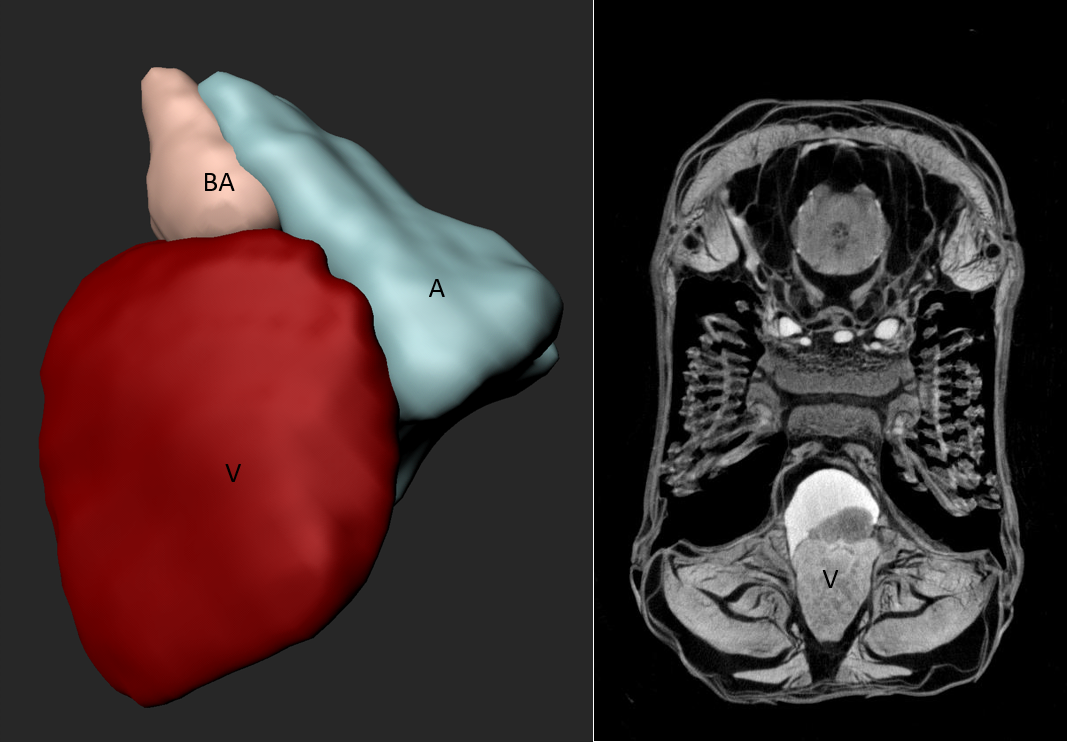

Fig. 11: Microcomputer tomography (µCT) of ex-vivo zebrafish heart. (a) fixed ……..X-ray voltage: 55 KV, X-ray current: 72 µA, filter: Al 0.25 mm, image pixel size: 2.9 µm, tomographic rotation: 180°, rotation step: 0.250°, frame averaging: 4, scan duration: 1h11min. Pictures provided by Anabela Bensimon-Brito, Department III.